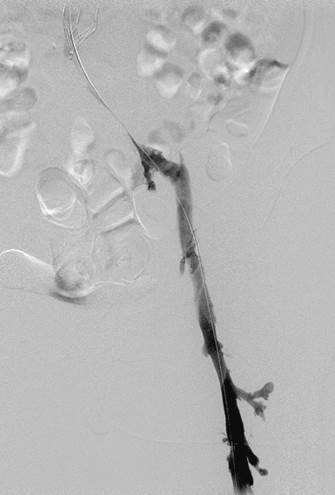

Venograma en posición de decúbito prono de la rama ilíaca izquierda que indica una estenosis causada por el tumor que comprime la uretra y la vena ilíaca externa izquierda.